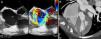

A 44-year-old woman with a prosthetic aortic valve was admitted to the cardiology department with shortness of breath and a new diastolic murmur. Transthoracic (TTE) and transesophageal echocardiography (TEE) were performed, the latter revealing a fistula between the aortic root and the right atrium (Figure 1A). Although blood cultures were negative, the final diagnosis was endocarditis. Prior to surgery, cardiac computed tomography (CT) confirmed the presence of a subaortic fistula (Figure 1B).